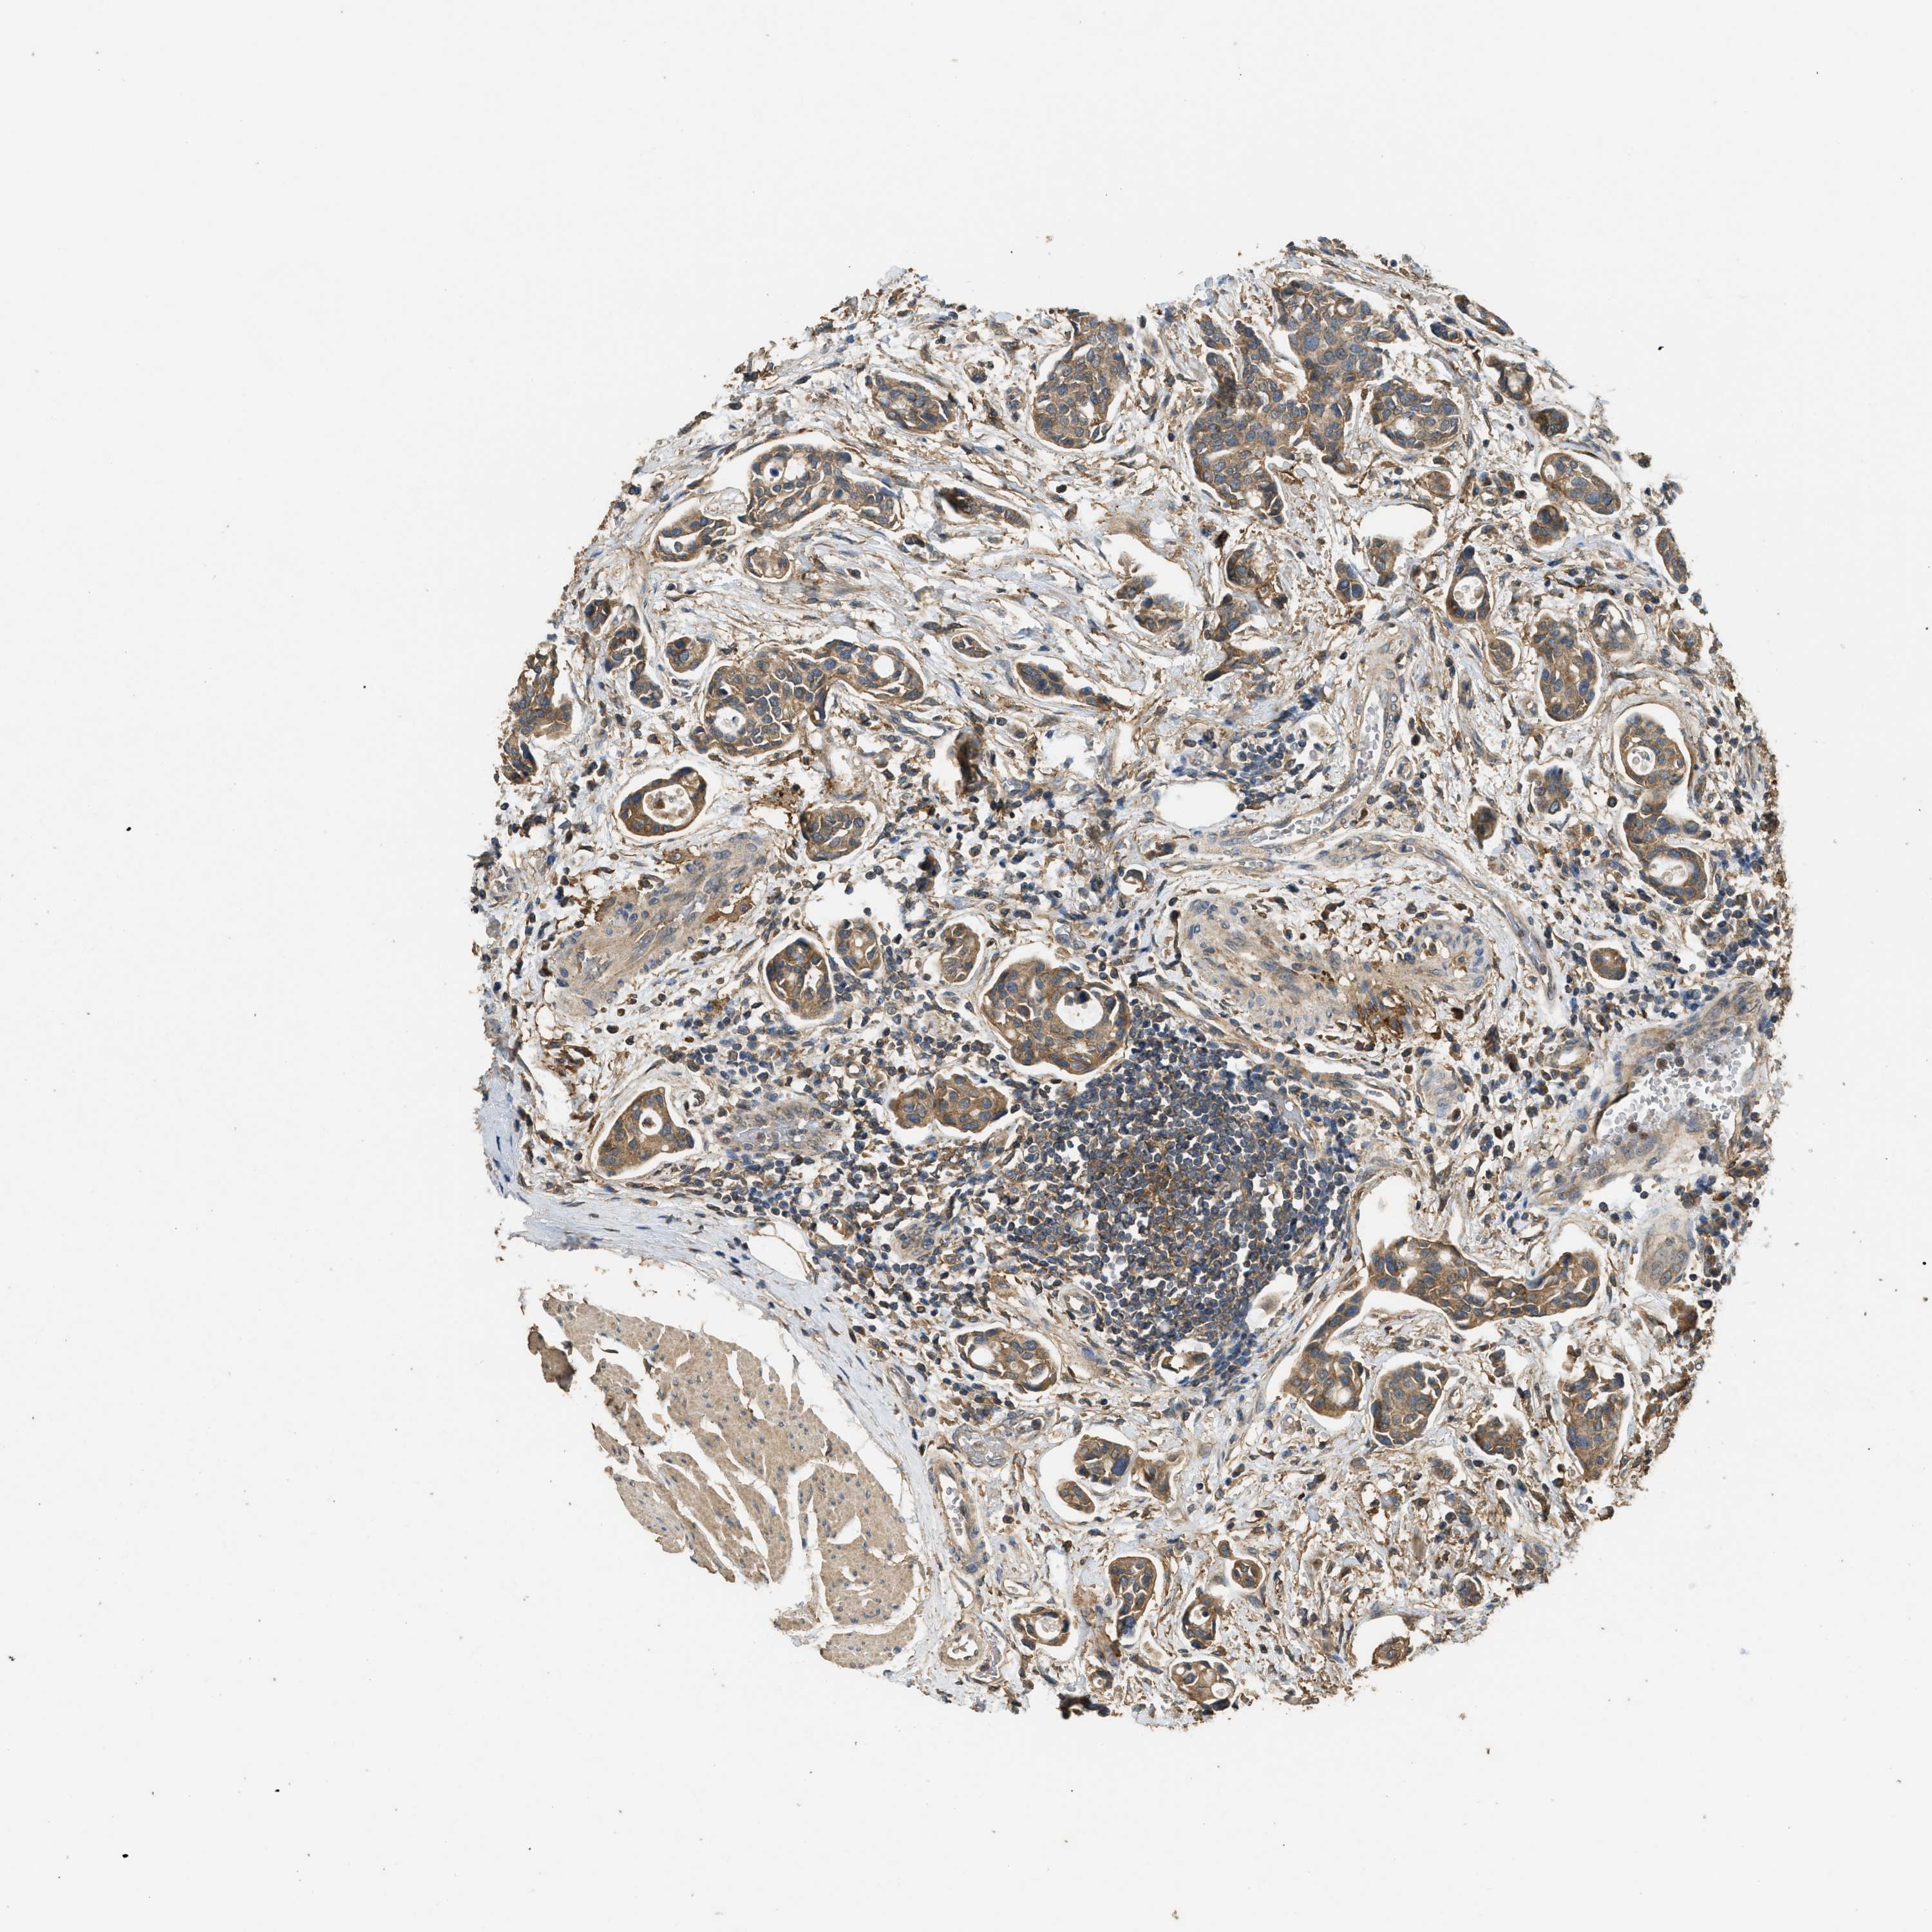

UROTHELIAL CANCER - Protein expressioni

A mouse-over function shows sample information and annotation data. Click on an image to view it in a full screen mode. Samples can be filtered based on level of antibody staining by selecting one or several of the following categories: high, medium, low and not detected. The assay and annotation is described here.

Note that samples used for immunohistochemistry by the Human Protein Atlas do not correspond to samples in the TCGA dataset.

Antibody stainingi

Antibody staining in the annotated cell types in the current human tissue is reported as not detected, low, medium, or high, based on conventional immunohistochemistry profiling in selected tissues. This score is based on the combination of the staining intensity and fraction of stained cells.

Each image is clickable and will lead to virtual microscopy that enables deeper exploration of all samples and also displays staining intensity scores, fraction scores and subcellular localization as well as patient and tissue information for each sample.

Antibody HPA009285

Antibody HPA017139

Antibody CAB017826

Staining

High

Medium

Low

Not detected

Intensity

Strong

Moderate

Weak

Negative

Quantity

>75%

75%-25%

<25%

None

Location

Nuclear

Cytoplasmic/membranous

Cytoplasmic/membranous,nuclear

Urothelial carcinoma, Low grade

Urothelial carcinoma, High grade